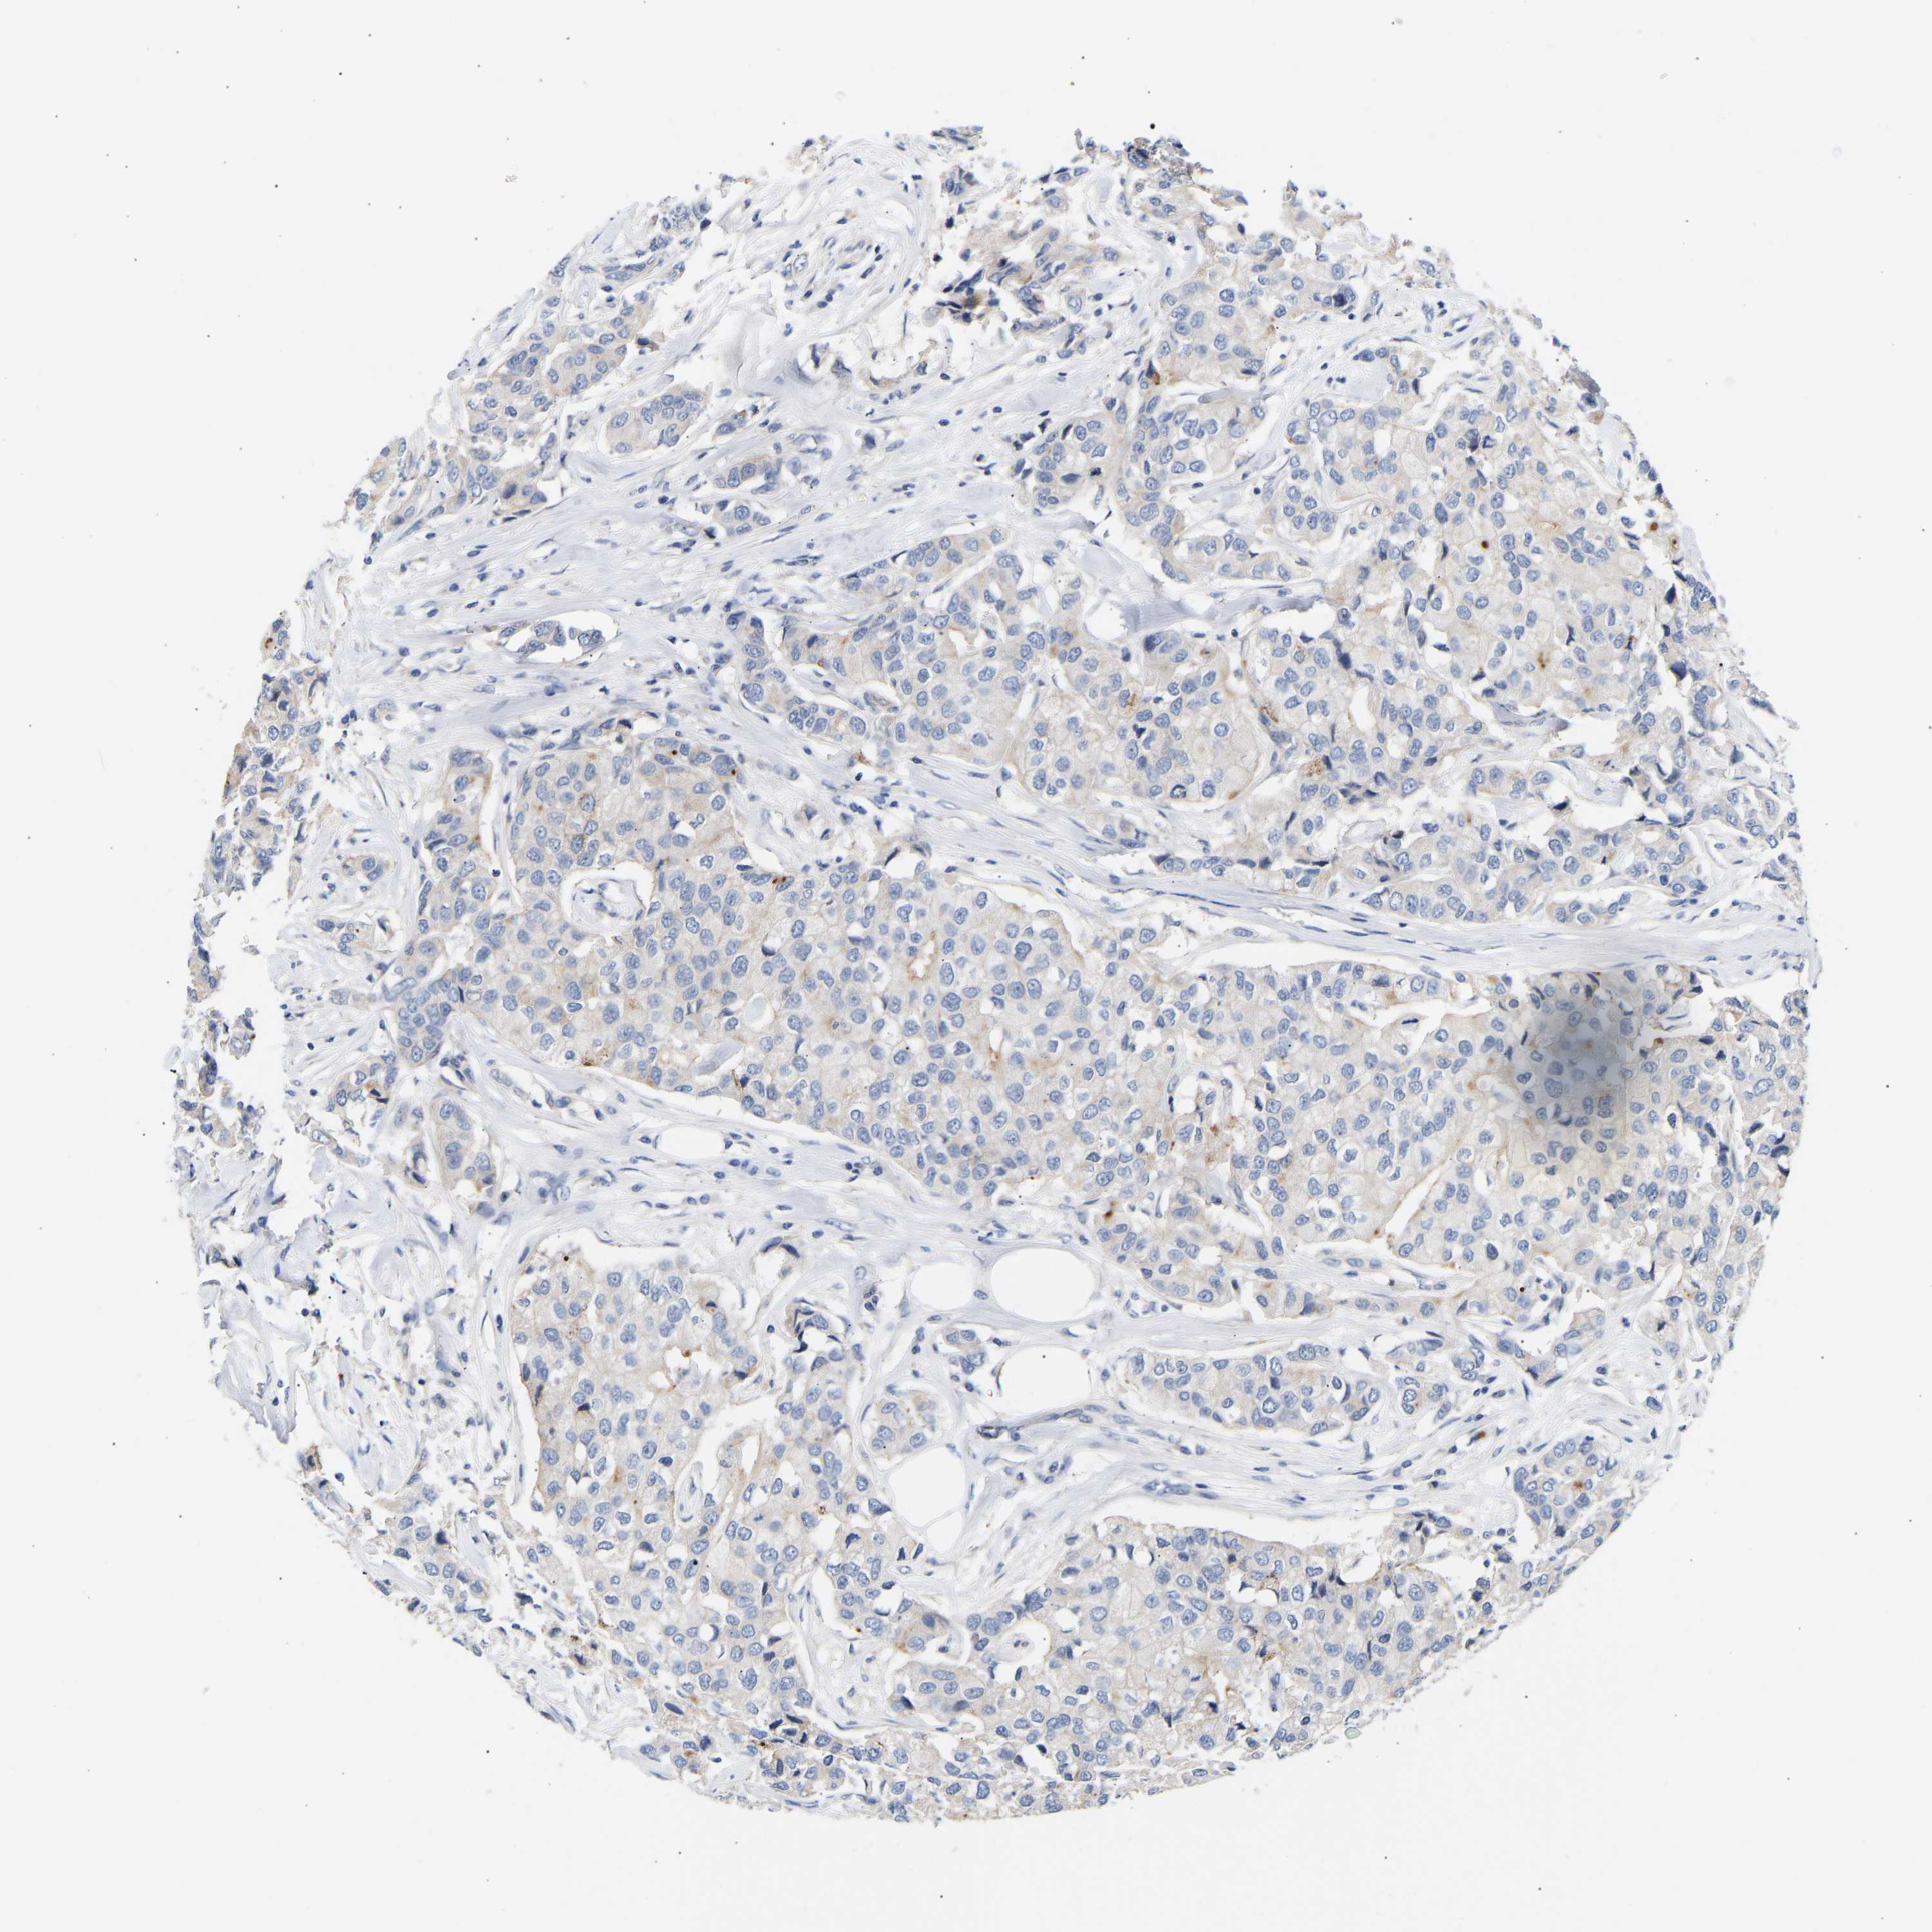

CANCER BREAST CANCER Show tissue menu

BRCA TCGA BRCA VALIDATION PROTEIN EXPRESSION